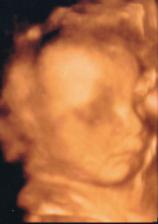

23.11. 3D UTZ na poliklinice Škodovky v Mladé Boleslavi. Byl to úžasný zážitek. Malá se hezky ukázala, má 681g. Všechny míry jsou v normě. Už víme, že nosík má po mamince a bradičku po tatínkovi🙂